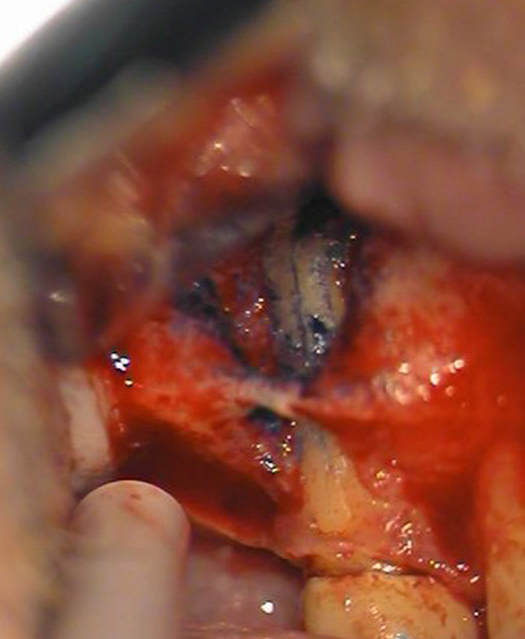

Sprickan börjar vanligen marginalt, men kan också börja apikalt (se bild 1 och 2) eller i mer ovanliga fall mitt på roten. Startar sprickan marginalt uppstår ofta en lokal djup tandköttsficka. Börjar sprickan längre apikalt kan den vara svårare att diagnostisera kliniskt och i dessa fall ger röntgen sällan någon information om diagnosen.